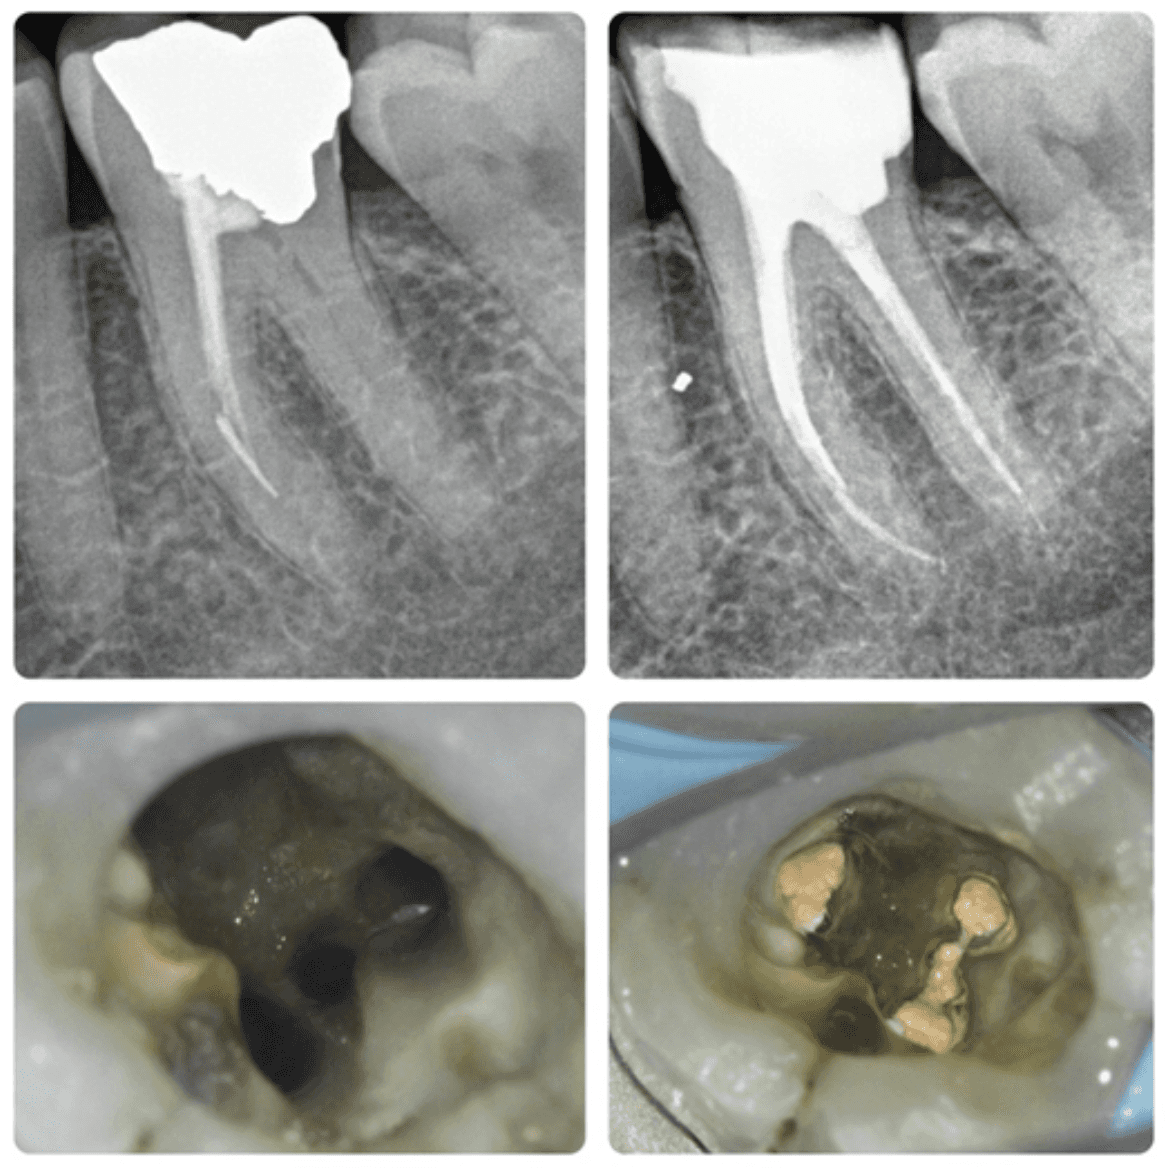

KREENA'S CASES